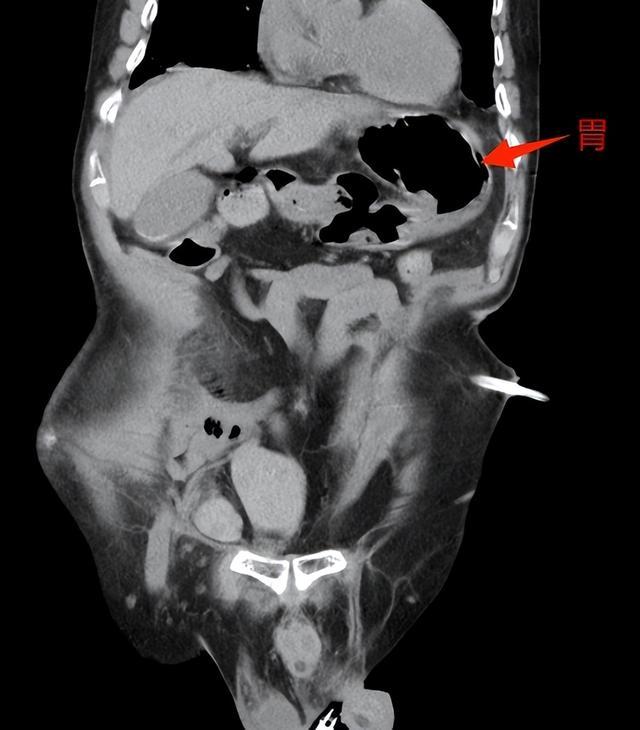

▲术后,胃及横结肠归于腹腔

术后,患者恢复良好,呕吐症状消失,顺利出院。